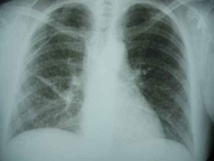

La tuberculeuse continue de faire des ravages au Sénégal. Si le traitement (gratuit) et le dépistage de la maladie restent une réussite, la transmission continue de gagner du terrain. Une remarque faite par la coordonnatrice du Programme national de lutte contre la maladie, docteur Marie Sarr Diouf. Pour y remédier, un Réseau national, piloté par Mamadou Niang, a été mis en place la semaine dernière pour lutter contre la pandémie.

Pour la coordinatrice du programme national de lutte contre la tuberculose, docteur Marie Sarr Diouf, l’initiative est à saluer. «Nous avons connu un succès dans le traitement des malades, le taux d’abandon est devenu très minime, idem pour le dépistage. Mais, nous constatons que la maladie est toujours là et la transmission continue à gagner du terrain», a-t-elle laissé entendre. Et de poursuivre: «notre objectif, c’est d’éradiquer la pandémie avant 2030. Avec le réseau, c’est une autre approche qui se dessine. Nous irons jusque dans les prisons, les marchés, aidé par l’association, pour trouver les malades et les prendre en charge».